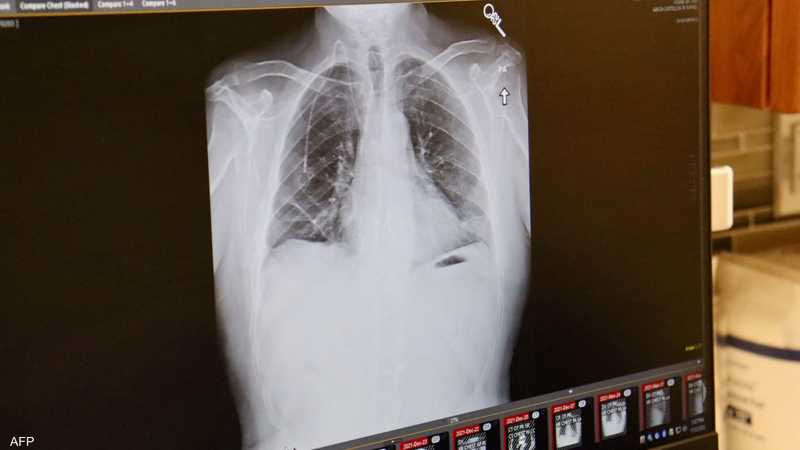

بعد التدخين.. سبب آخر خطير يسبب الإصابة بسرطان الرئة

قال باحثون من جامعة كاليفورنيا، يوم السبت، إن تلوث الهواء يرتبط بشكل وثيق بطفرات في الحمض النووي مرتبطة بسرطان الرئة، حتى لدى الأشخاص الذين لم يسبق لهم التدخين.